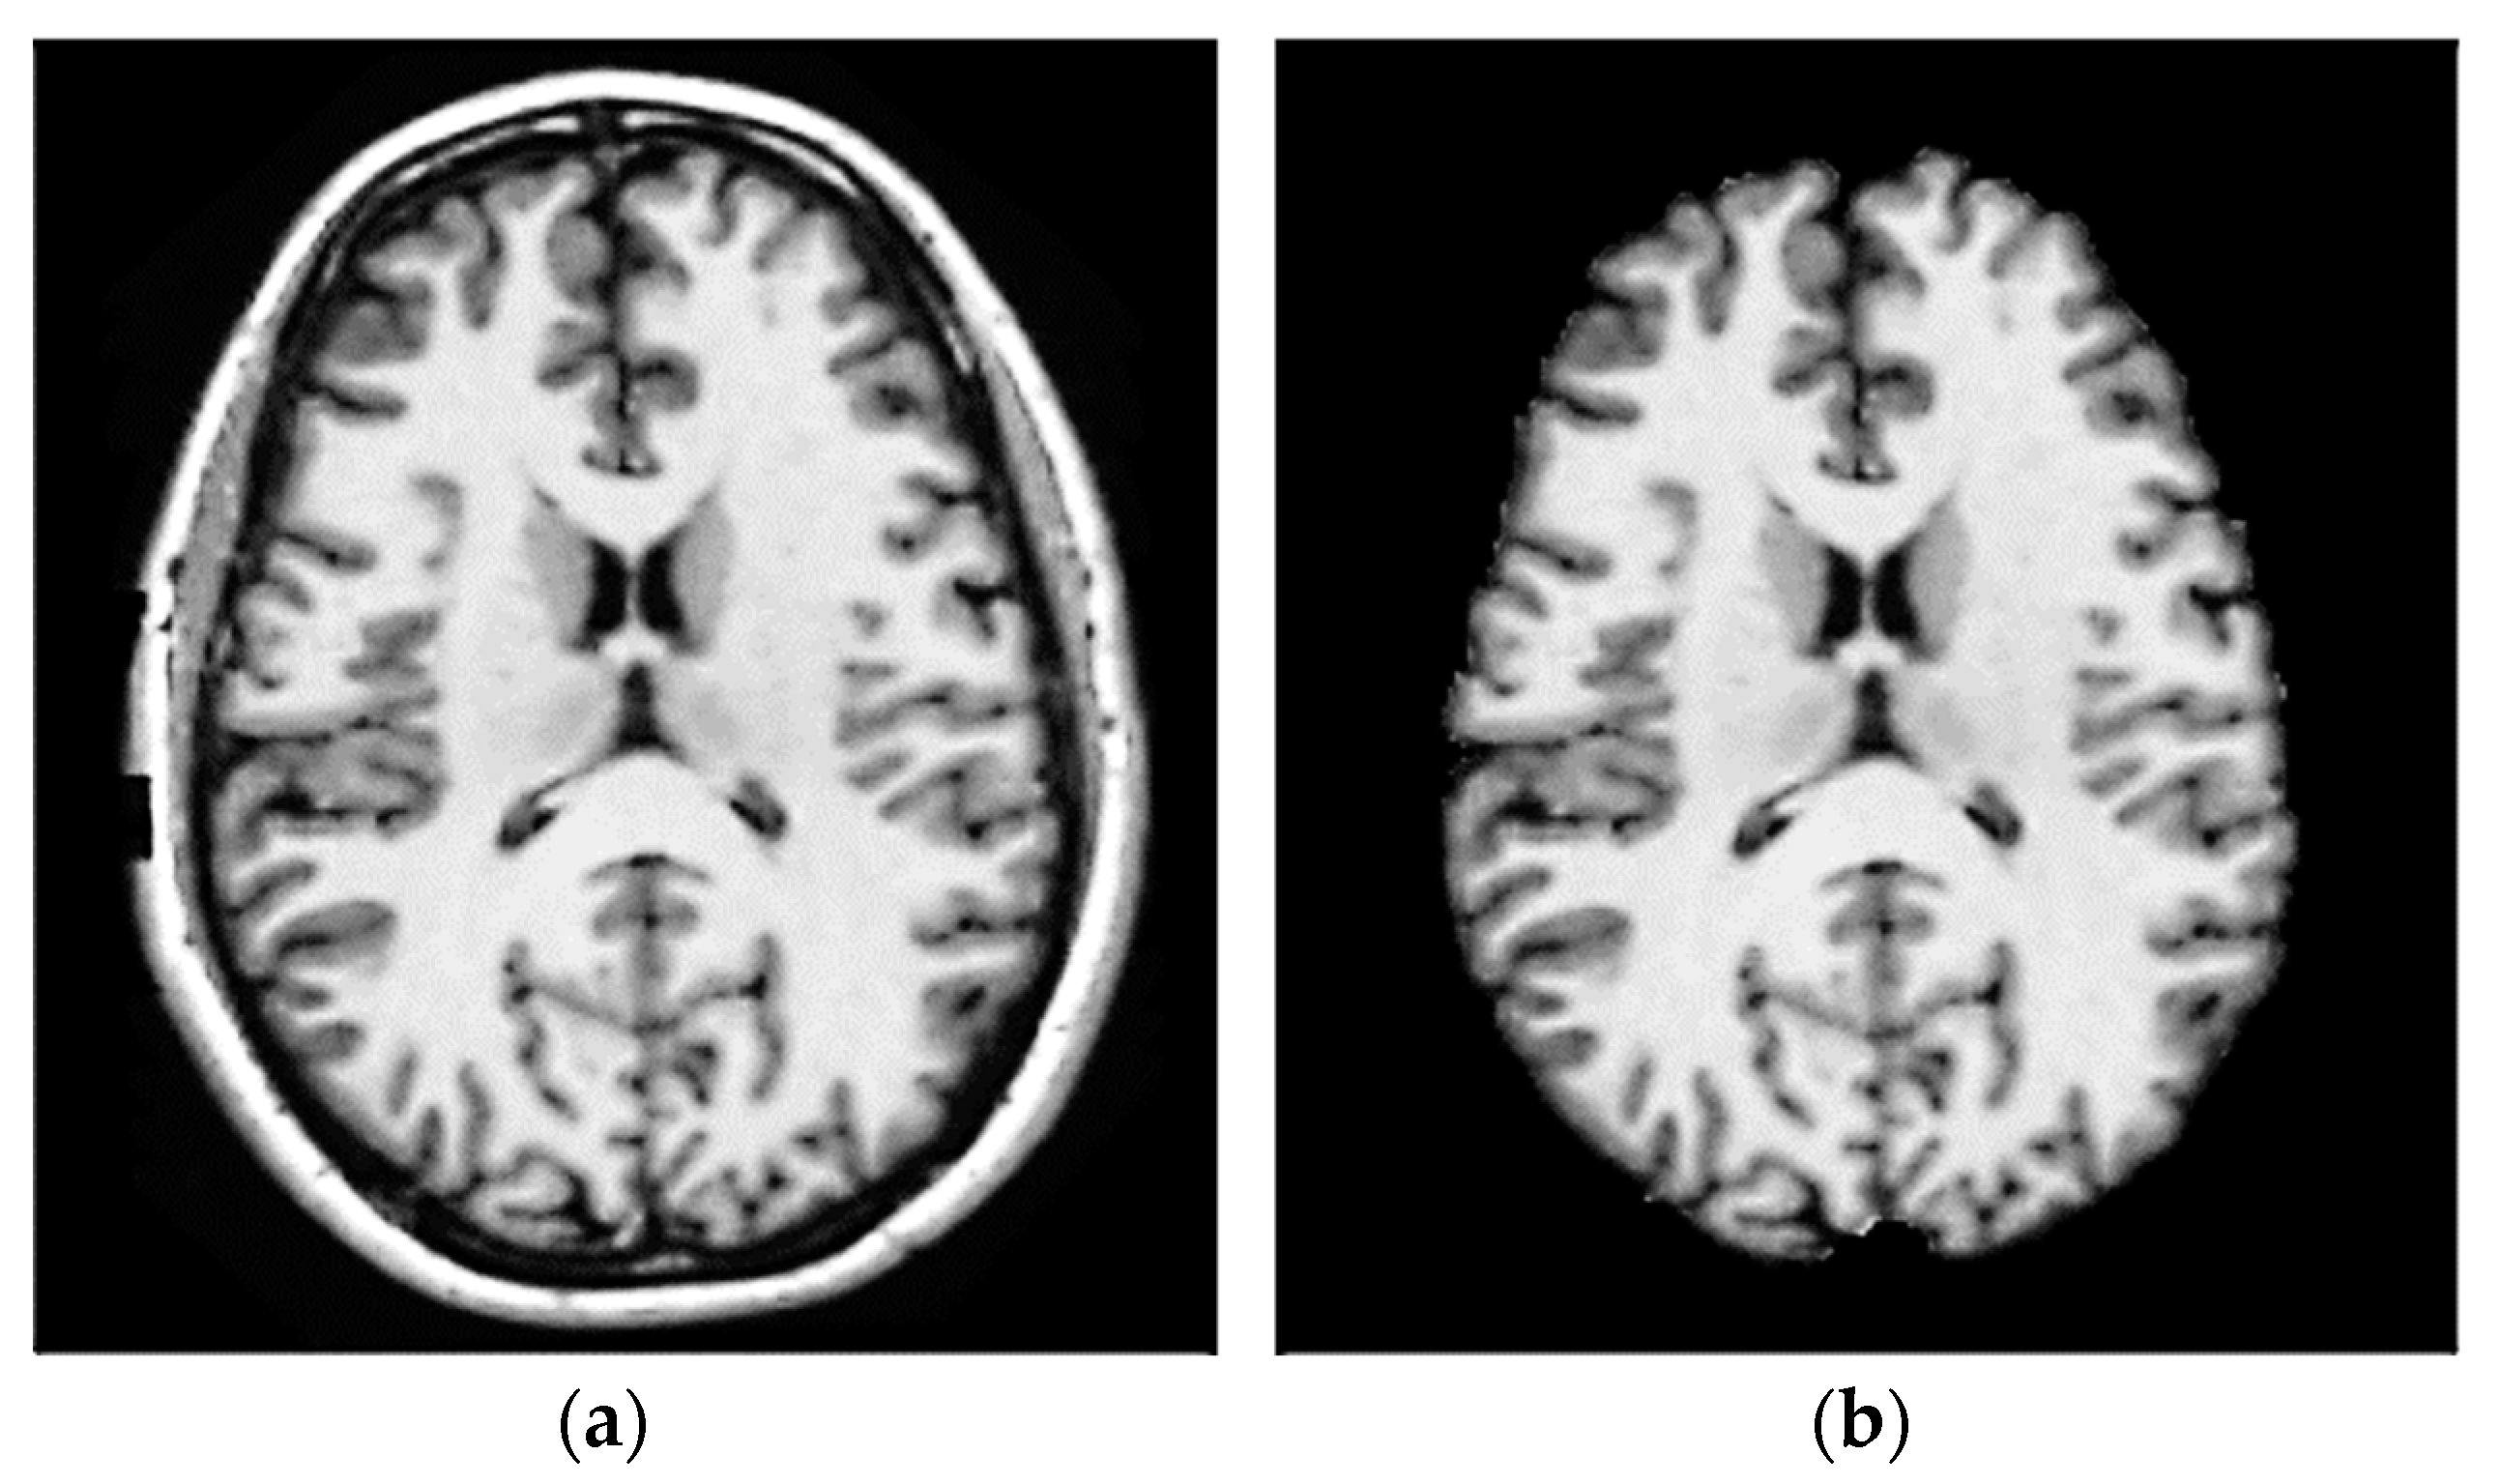

3.1. Step 1 Preprocessing Phase

- Nair, R.; David, E.; Rajagopal, S. A robust anisotropic diffusion filter with low arithmetic complexity for images. EURASIP J. Image Video Process. 2019, 2019, 48. [Google Scholar] [CrossRef]